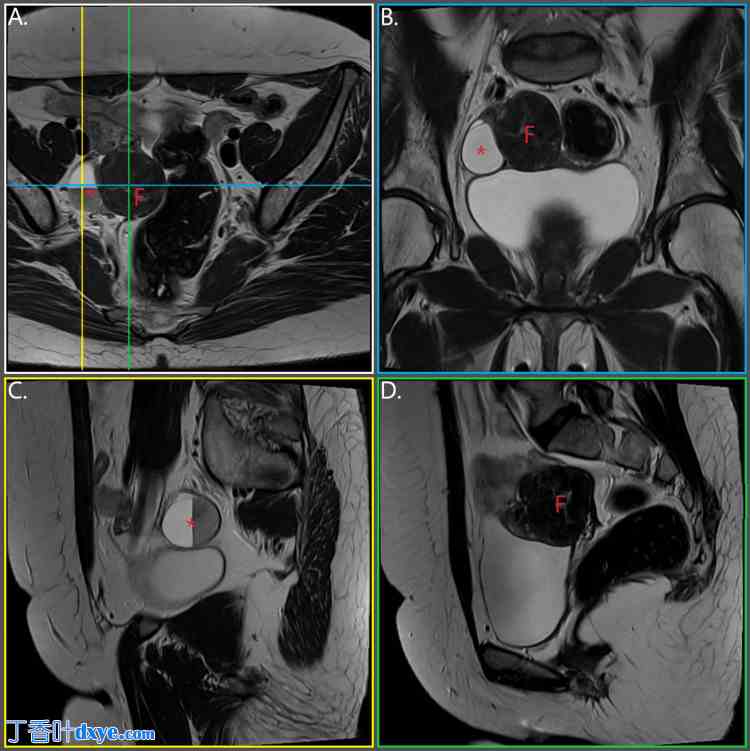

就诊前三个月,在例行妇科检查中,患者被诊断出右侧卵巢有一个直径约3厘米的较大囊性肿块,以及盆腔内有一个直径约4厘米的肿块。超声检查结果主要表现为间叶组织来源的肿块;然而,鉴别诊断包括盆腔脓肿、卵巢或卵巢旁肿块以及输卵管积水。鉴于卵巢囊肿的可疑特征、患者的年龄、MRKH综合征导致的盆腔解剖结构异常以及盆腔内存在不明肿块,其妇科医生建议她进行下腹部和盆腔MRI检查,她于一个月后(即来院就诊前两个月)完成了检查。该检查证实右侧卵巢对应解剖区域存在一个囊性病变,大小为3.8 x 3.4 cm,内部可见明显的液-液平面,提示为复杂性出血性囊肿。此外,盆腔内还发现一个类似子宫肌瘤的异质性肿块,大小为4.4 x 3.8 cm(图1)。

图 1. 术前盆腔及下腹部 MRI 扫描,多平面重建。

F:子宫肌瘤;*:卵巢囊肿

(A) 横断面;(B) 冠状面(蓝色);(C) 纵断面,卵巢囊肿水平(黄色);(D) 纵断面,子宫肌瘤水平